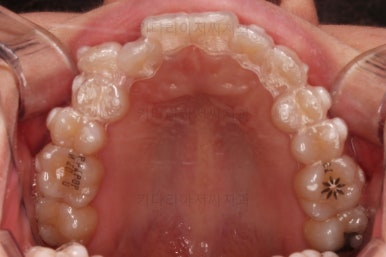

삐뚤한 덧니를 가지런하게 하기 위해서 필요한 부분의 어금니를 순차적으로 뒤로 밀어줍니다.

자세히 보면 치아 사이사이에 틈새가 생기는게 보이죠?

틈새를 일부러 만들어 해당 공간으로 덧니를 가지런하게 하는 원리입니다.

장치를 사용한지 1년 2개월째 사진입니다.

매우 가지런해졌죠.